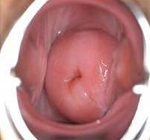

宫颈腺体囊肿(Nabothcyst)又叫宫颈纳氏囊肿,妇科、宫颈纳囊(可称“纳囊”),宫颈糜烂、息肉一样,是慢性宫颈炎的一种。其包含的粘液常清澈透明,但可能由于合并感染而呈混浊脓性。囊肿一般小而分散,突出于子宫颈表面。小的仅有小米粒大,大的可达玉米粒大,呈青白色,可能伴有糜烂,但亦常见于表面光滑的子宫颈。

治疗前

治疗后